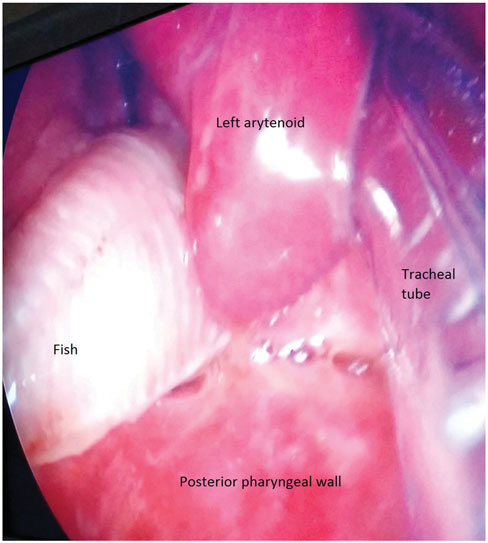

Trở lại với chàng thanh niên người Hà Lan đã nuốt con cá chuột. Các bác sĩ cuối cùng đã phải gây mê cho anh, đặt ống nội khí quản và dùng ống nội soi để tìm con cá trong hầu họng của anh ấy.

Một bác sĩ đã cẩn thận gắp được con cá ra ngoài, họ không còn cứu sống được nó nữa. Tất nhiên, con cá đã chết vì ngộ độc CO2 trong bia, hoặc đơn giản là nó đã phải ở ngoài bể nước của mình quá lâu.

Con cá (bên trái) mắc trong họng của thanh niên Hà Lan năm 2016 (Ảnh chụp nội soi của bác sĩ).